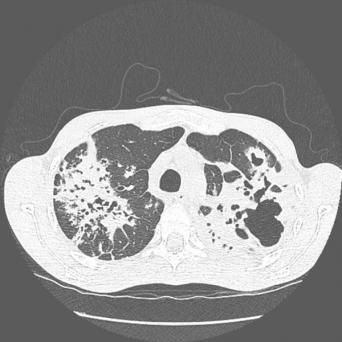

L’image

du jour

Illustration

Cancer de la prostate

Le « Movember » – qui se déroule chaque mois de novembre – a pour but de sensibiliser la population à la lutte contre les cancers masculins, dont le cancer de la prostate qui est en première position (26,5 % des cancers chez les hommes de plus de 65 ans).